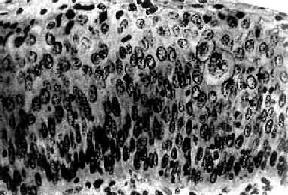

图13-3 子宫颈原位

变限于上皮层内,细胞核肥大、深染,大小不一,形态不规则,核仁明显,核分裂像易见,且见巨细胞(右侧上方),这种细胞间变累及上皮全层,但基底膜完整,细胞未浸润到基底膜下间质

子宫颈原位(carcinoma in situ)细胞局限于上皮全层内、尚未穿破上皮基底膜侵入下方固有膜。子宫颈原位的异型细胞比不典型增生者更具显着的多形性。镜下,上皮层完全为细胞所取代,细胞大小、形状不一,呈圆形、卵圆形、梭形,偶见巨核、多核,排列紊乱,层次不清,极向消失。核大浓染、大小及形状不一、染色质增粗,核分裂像常见,并有病理性核分裂像。胞浆相对减少,核浆比值增大(图13-3)。原位细胞可由表面沿基底膜伸入腺体内,致整个腺管或其一部分为细胞所取代,但腺管轮廓尚存,腺体基底膜完整,细胞未浸润到固有膜。这种变化称原位累及腺体。原位累及腺体并不一定发展为浸润。部分子宫颈原位可长期不发生浸润,个别病例甚至可自行消退。但由于原位特别是原位累及腺体具有发展为浸润的倾向,故一旦发现,应及时给予适当治疗。